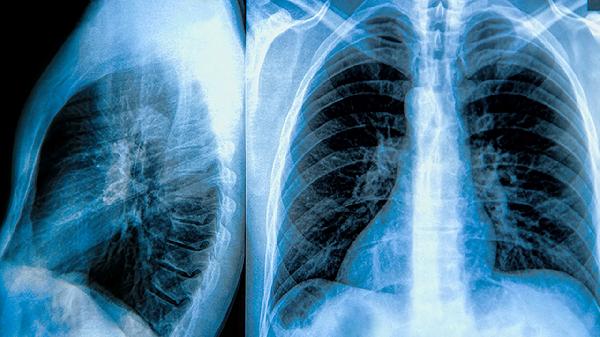

手术操作可能导致邻近肺组织损伤、出血或气胸加重,胸腔镜手术虽创伤较小,但存在中转开胸可能。复杂粘连或巨大肺大泡者手术难度更高。

肺组织愈合不良或新发肺大泡可能导致气胸复发,发生率约5%-10%。吸烟、慢性咳嗽等危险因素未控制者复发率更高。